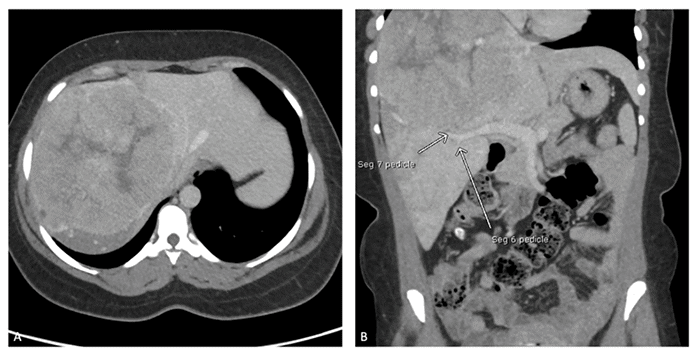

A 37-year-old female presented to an outside ER two weeks postpartum with severe right upper quadrant (RUQ) pain. Her past medical history was notable for chronic hepatitis B virus (HBV) infection. A CT scan revealed a 15 cm mass in the liver with evidence of intratumoral hemorrhage, primarily in the right lobe with extension into the left (Figure 1). There was no evidence of metastatic disease. Laboratory results were significant for an elevated alpha-fetoprotein (AFP) level of 521 ng/mL, a platelet count of 503,000/µL, and a total bilirubin of 0.8 mg/dL. As expected, HBV markers were positive. Percutaneous liver biopsy confirmed moderately differentiated hepatocellular carcinoma (HCC). The patient was subsequently transferred to our institution for further management.

Figure 1. Preoperative CT Scan Depicting Tumor and Segment Pedicles. Published with Permission

(A) Axial view demonstrating a large, centrally located hepatocellular carcinoma. (B) Coronal view showing the vascular pedicles to segments 6 and 7 (white arrows)